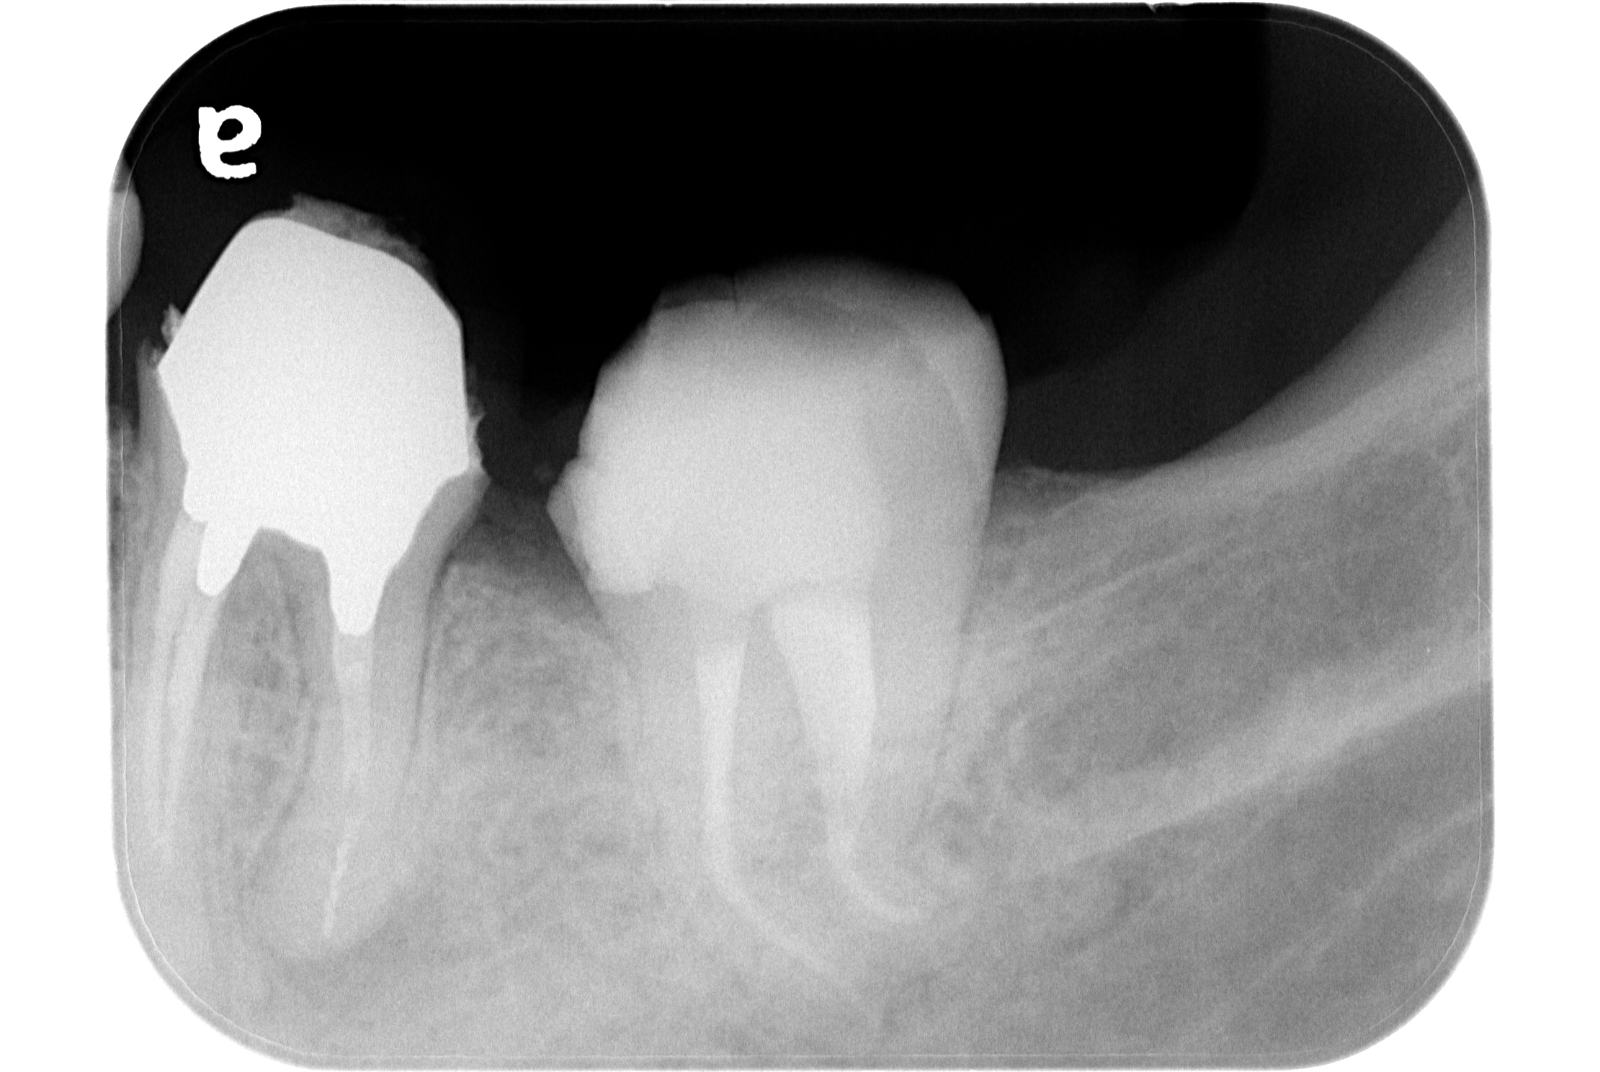

治療例 写真とレントゲン

治療前

治療後

※治療例に記載の情報はあくまでも症例に対してのものとなります。

| 費用 | 外科的歯内療法 (1年以内) 143,000円(税込) |

|---|---|

| 治療期間 | 1日 |

| 治療回数 | 1回 |

| 主な副作用とリスク | 術後に歯内退縮を起こすことがあります。 歯根破折を認めた場合、保存不可能と判断する場合があります。 |